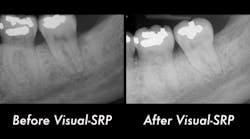

A clinical periodontal and radiographic assessment is completed. Although there is moderate bone loss in all four quadrants, his periodontal status is stable with the exceptions of Nos. 18 and 31 distal (figures 1 and 2). Both areas reveal direct distal probing depths of at least 10 mm and radiographic infrabony distal defects.

Figure 1: No. 18

Figure 2: No. 31

Many periodontists find these defects very predictable to treat with surgery and bone regenerative materials. The high peak of remaining bone provides support, blood supply, and biologic assistance to the grafted area. Conversely, this area tends to be very difficult to treat nonsurgically. Accessing the direct distal of these teeth is extremely challenging, and at depths beyond 5–6 mm, the results of the nonsurgical approach are expected to be poor.